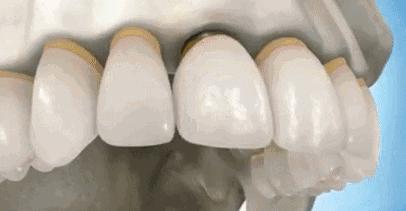

2,省略种植步骤。种植体手术一般分为一期和二期手术,在一期种植体植入后会先安装临时的愈合基台,在二期安装永久基台和修复牙冠,但有些低价种植手术会省略一些必要的步骤,这给患者今后的愈合留下了极大的隐患,也有可能会降低患者之后种植体的使用体验。